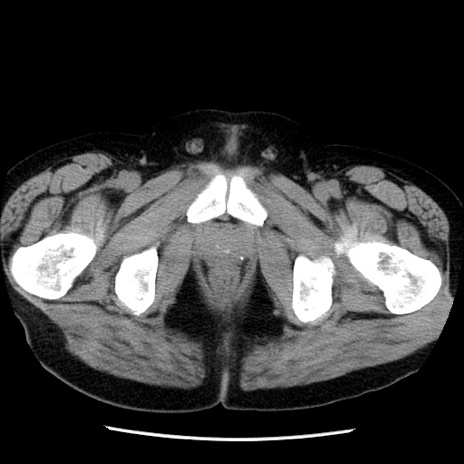

症例29(横断像)

【症例】40歳代男性

【現病歴】2日前から胃痛あり。徐々に周期的な激痛に変化した。本日になっても激痛があるため受診。

【身体所見】意識清明、BT 38-39℃台あり、腹部:膨満、やや硬、右下腹部に圧痛あり。

【データ】WBC 8500、CRP 23.26